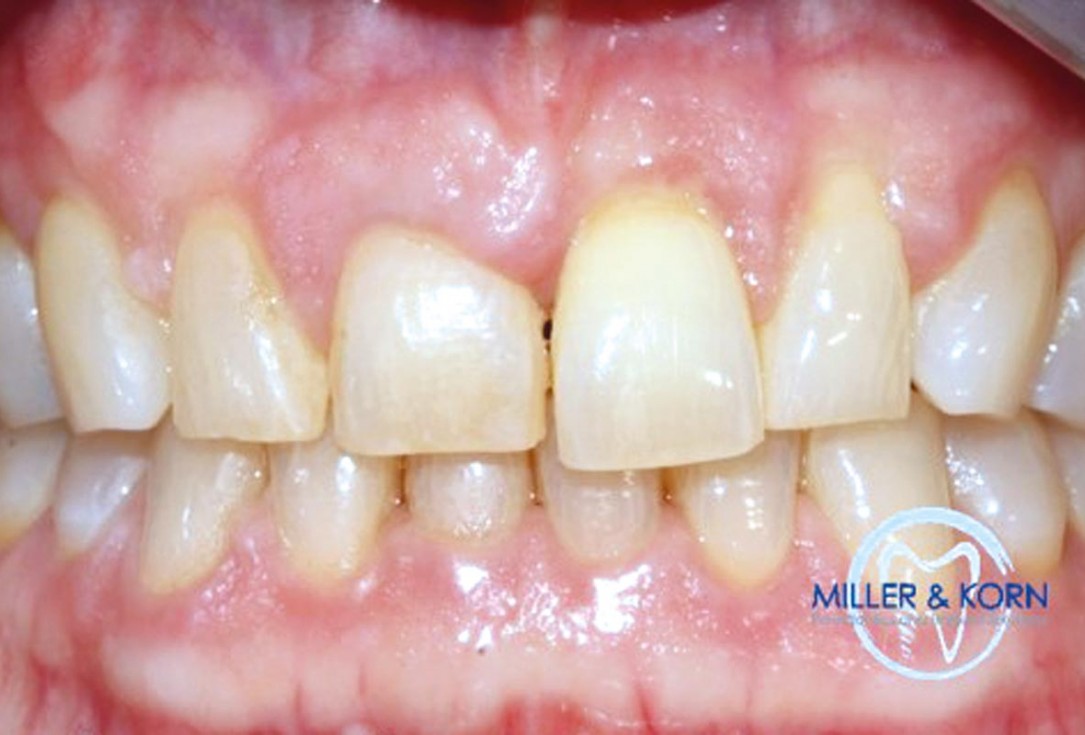

01/39 - The patient presented with pathologic mobility of upper left central incisor. Radiographic examination revealed significant circumferential attachment loss with an unfavorable crown to root ratio.Immediate implant placement and correction of horizontal and vertical bone loss using an allograft bone ring, cerabone® and Jason® membrane - Drs. Miller and Korn

The patient presented with pathologic mobility of upper left central incisor. Radiographic examination revealed significant circumferential attachment loss with an unfavorable crown to root ratio.